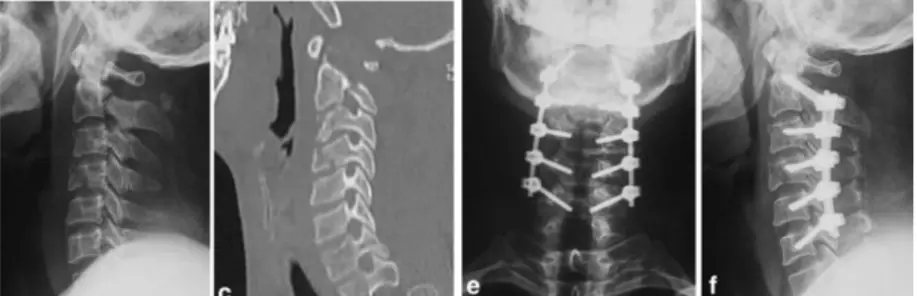

Cervical Facet Dislocations

- Spectrum of traumatic injuries with varying degrees of cervical instability and risk of spinal cord injury

- Diagnosis: Confirmed with radiographs or CT scan

- MRI: Should be performed before surgery to identify associated disk herniation

- Treatment: Closed or open reduction, followed by surgical stabilization

Surgical Fixation Techniques